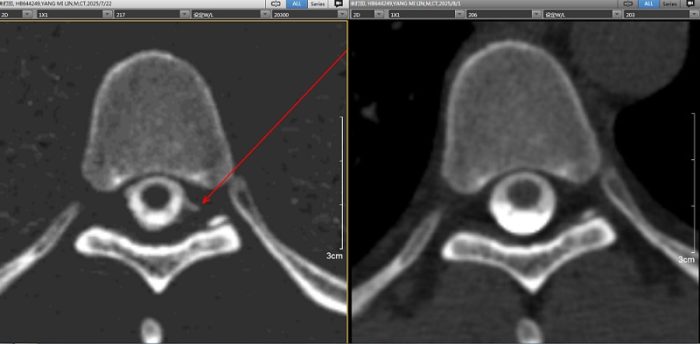

在海南医院放射诊断科的紧密协作下,医疗团队通过腰肢穿刺,将一种非常安全的非离子型造影剂(碘海醇)注入患者杨先生的蛛网膜下腔。随着造影剂在脑脊液循环的流动下,高分辨率的CT扫描开始了“地毯式”搜索。果然,图像清晰显示,造影剂在胸8椎体水平的位置从硬脊膜漏出,“瘘口找到了!尽管非常小,但正是它导致患者反复发作的头痛头晕”,汤浩说,脑脊液漏是颅脑创伤的典型并发症,利用CTC技术能够快速精准诊治病情,对于挽救患者生命、降低伤残率至关重要。

尽管明确了杨先生病灶漏点位置,但基于病灶的瘘口较小,医疗团队为他制定了以严格卧床、加强补液为主的保守治疗方案。汤浩说,经过一段时间的补液保守治疗,杨先生的“直立性头痛”症状完全消失,摆脱了困扰他数月的头痛头晕阴霾。经复查CT脑池造影术确认,患者之前的瘘口已愈合至完全消失。

椎管造影轴位图。左图为术前影像,箭头所示为瘘口位置;右图为术后影像图,复查后显示已愈合呈消失状态。